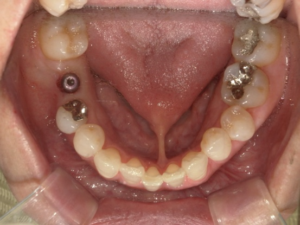

(治療後)

インプラントは単独での補綴物になるため、隣接歯への影響はなく、噛み合わせの再現もできる唯一の補綴物です。

傷口が小さく、術後の疼痛もほとんどありませんでした。

経過も良好で、問題なく過ごしています。